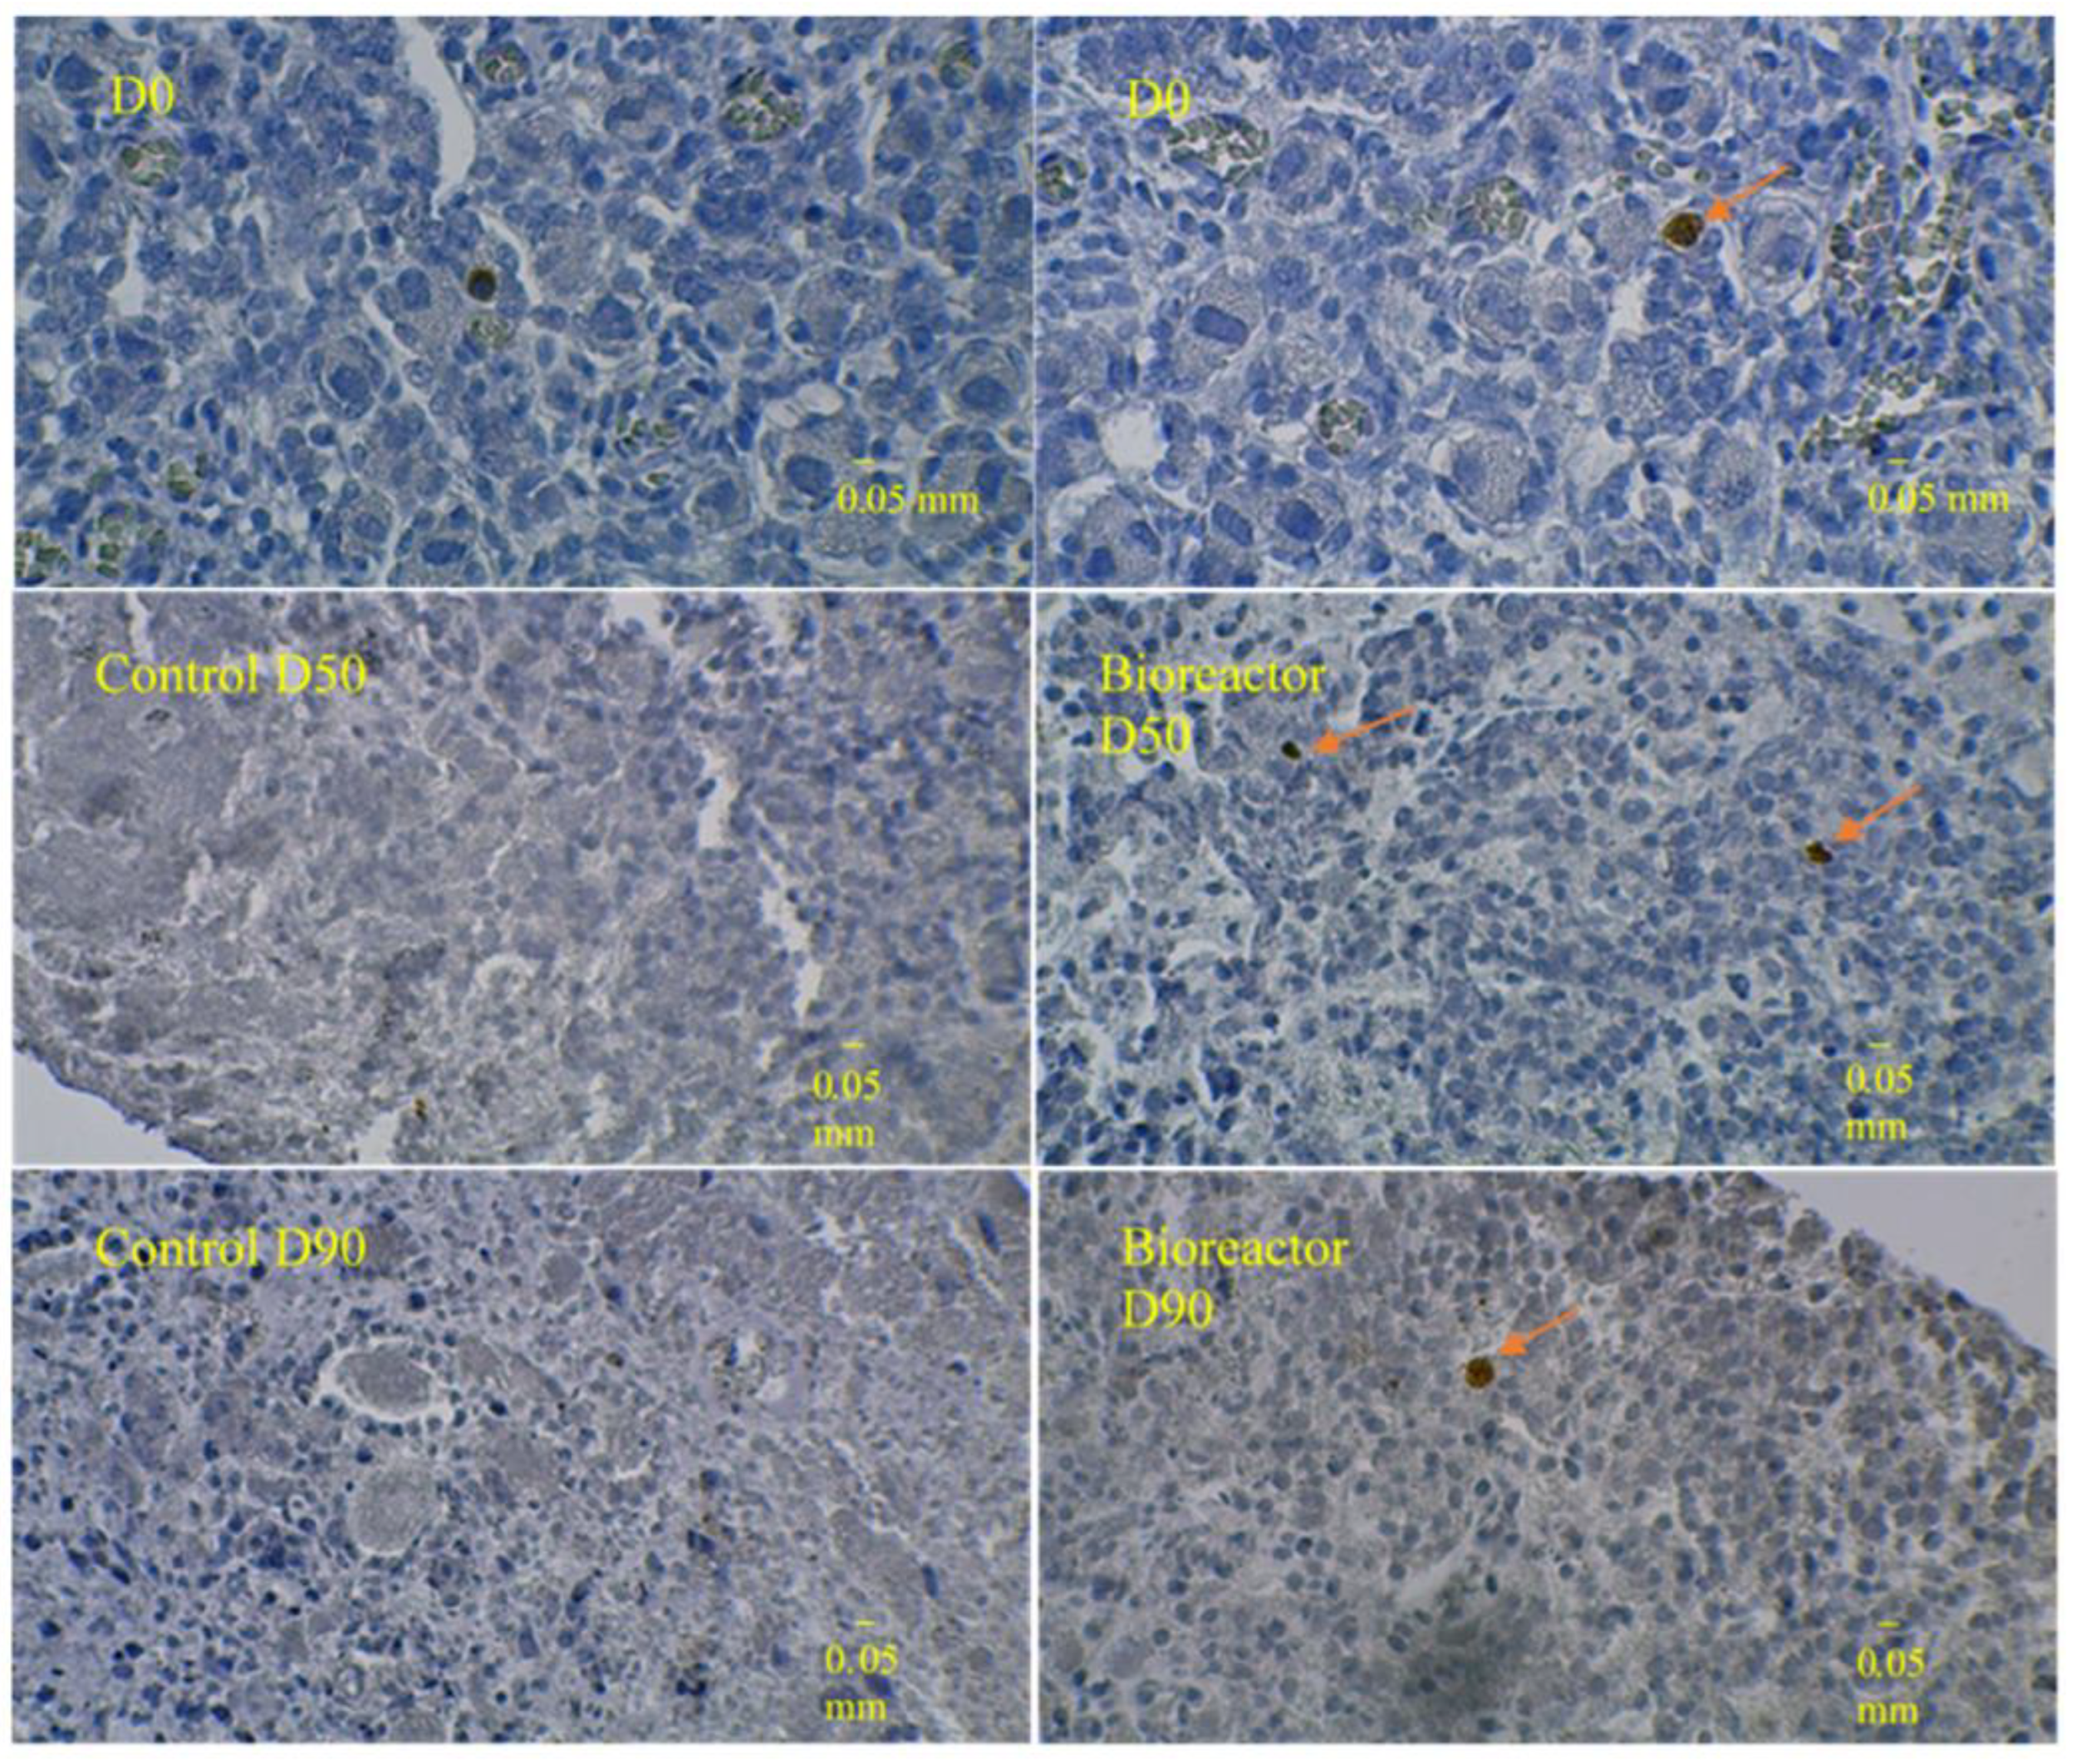

3.3. Immunostaining for Cell Apoptosis